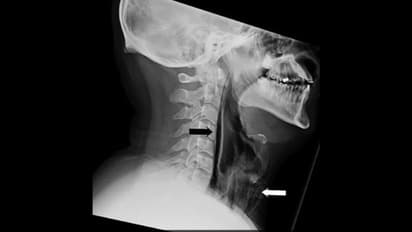

അങ്ങനെ ഇദ്ദേഹം ഡോക്ടറെ കണ്ടു. വിശദമായ പരിശോധനയിലാണ് അന്നത്തെ ശക്തമായ തുമ്മലാണ് ഇദ്ദേഹത്തിന് വിനയായത് എന്ന് മനസിലായത്. അതിശക്തമായി തുമ്മിയതോടെ തൊണ്ടയില് കീറല് വീഴുകയായിരുന്നുവത്രേ. 'ഫാരിംഗ്സ്' എന്ന ഭാഗത്താണ് പരുക്ക് പറ്റിയത്. ഇതോടെയാണ് വേദനയും അസ്വസ്ഥതയുമെല്ലാം തുടങ്ങിയത്.